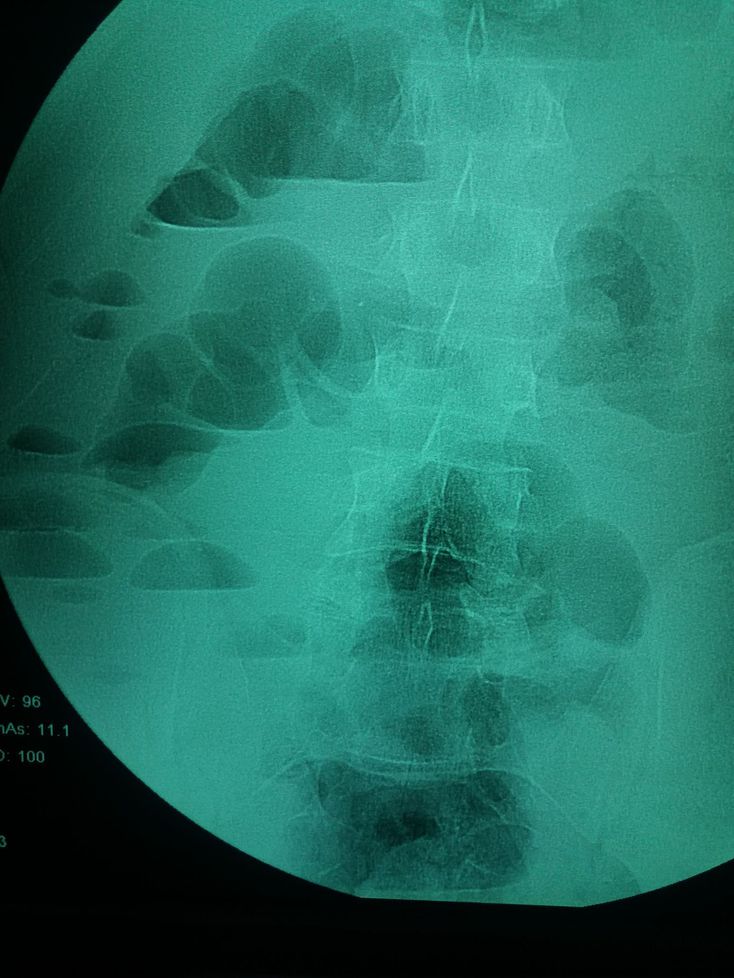

What do you see

Multiple air-fluid levels which indicate GI obstruction

Step ladder pattern/ Air fluid levels in X Ray abdomen, most likely intestinal obstruction